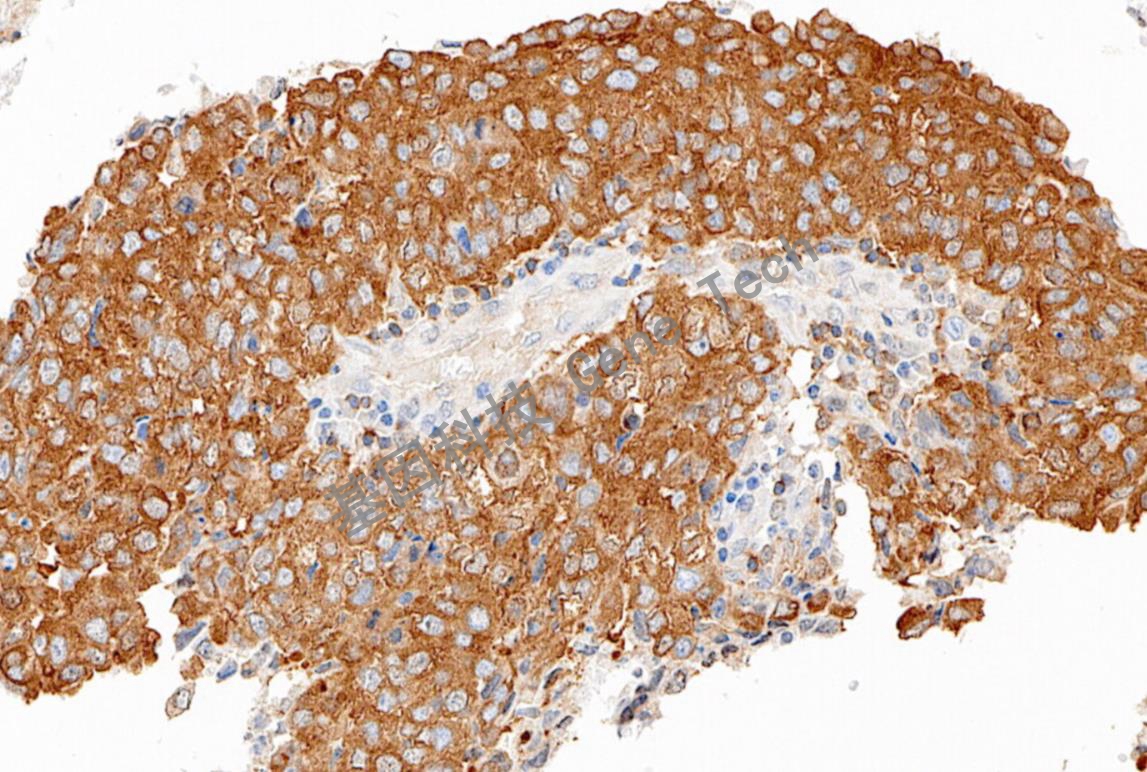

| 克隆號(hào):E-10 | 種屬:鼠 | 適用染色系統(tǒng):GTvisionTM |

| 預(yù)處理:高pH熱修復(fù) | 陽(yáng)性部位:細(xì)胞漿 | 陽(yáng)性對(duì)照:胃癌/闌尾 |

| 簡(jiǎn)介:NF- κ B(Nuclear factor kappa-B, 核因子 κ B)是由一組結(jié)構(gòu)上相關(guān)的蛋白質(zhì)家族組成,包括RelA(p65),C-Rel,NF-KB1(P50/P105),NFKB2(P52/P100)。NF-KB由兩個(gè)屬于Rel家族的亞單位以同源或異源二聚體構(gòu)成,可誘導(dǎo)的形式是由有NF- κ B和Rel組成的異源二聚體,主要發(fā)揮作用的是P50/P65異源二聚體。NF- κ B主要參與抗體免疫功能的調(diào)解,可調(diào)控與炎癥反應(yīng)和免疫反應(yīng)有關(guān)的許多細(xì)胞因子、粘附分子基因的表達(dá),用于各種疾病的研究。 | ||

| 鱗狀細(xì)胞癌石蠟切片,用 NF Kappa B/p50(GT2384)染色,細(xì)胞漿陽(yáng)性,DAB 顯色。 | ||